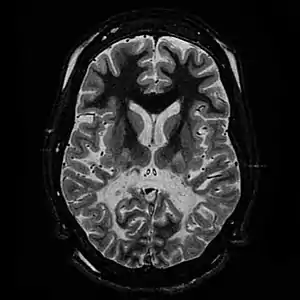

| White matter, with reduced volume and increased signal intensity. The anterior white matter is spared. Features are consistent with X-linked adrenoleukodystrophy. | |